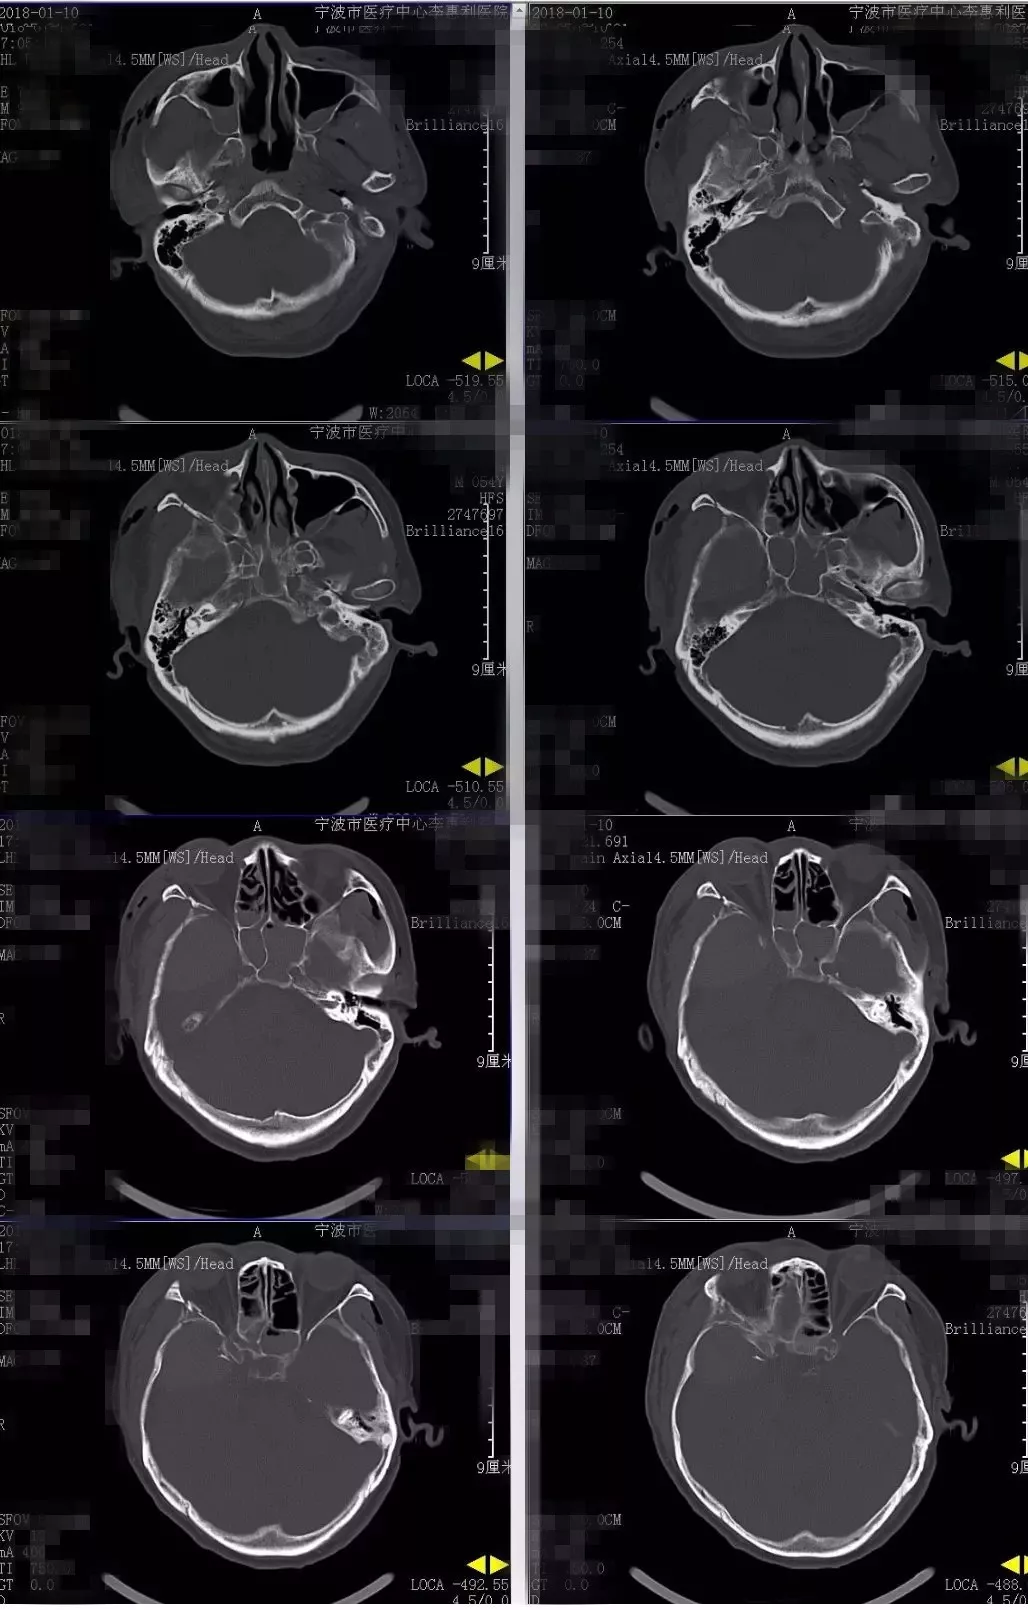

辅助检查:2018-1-10复查头部及胸部CT:右颞部硬膜外血肿。右侧颞骨、颧弓骨折,右侧颅底多发骨折(图1)。右侧液气胸,胸腔引流管在位。右侧多发肋骨骨折。右肱骨正侧位片:右侧肱骨下端粉碎性骨折。

图1. 2018-1-10入院时头CT:右颞部硬膜外大血肿。右侧颞骨、颧弓骨折,右侧颅底多发骨折。